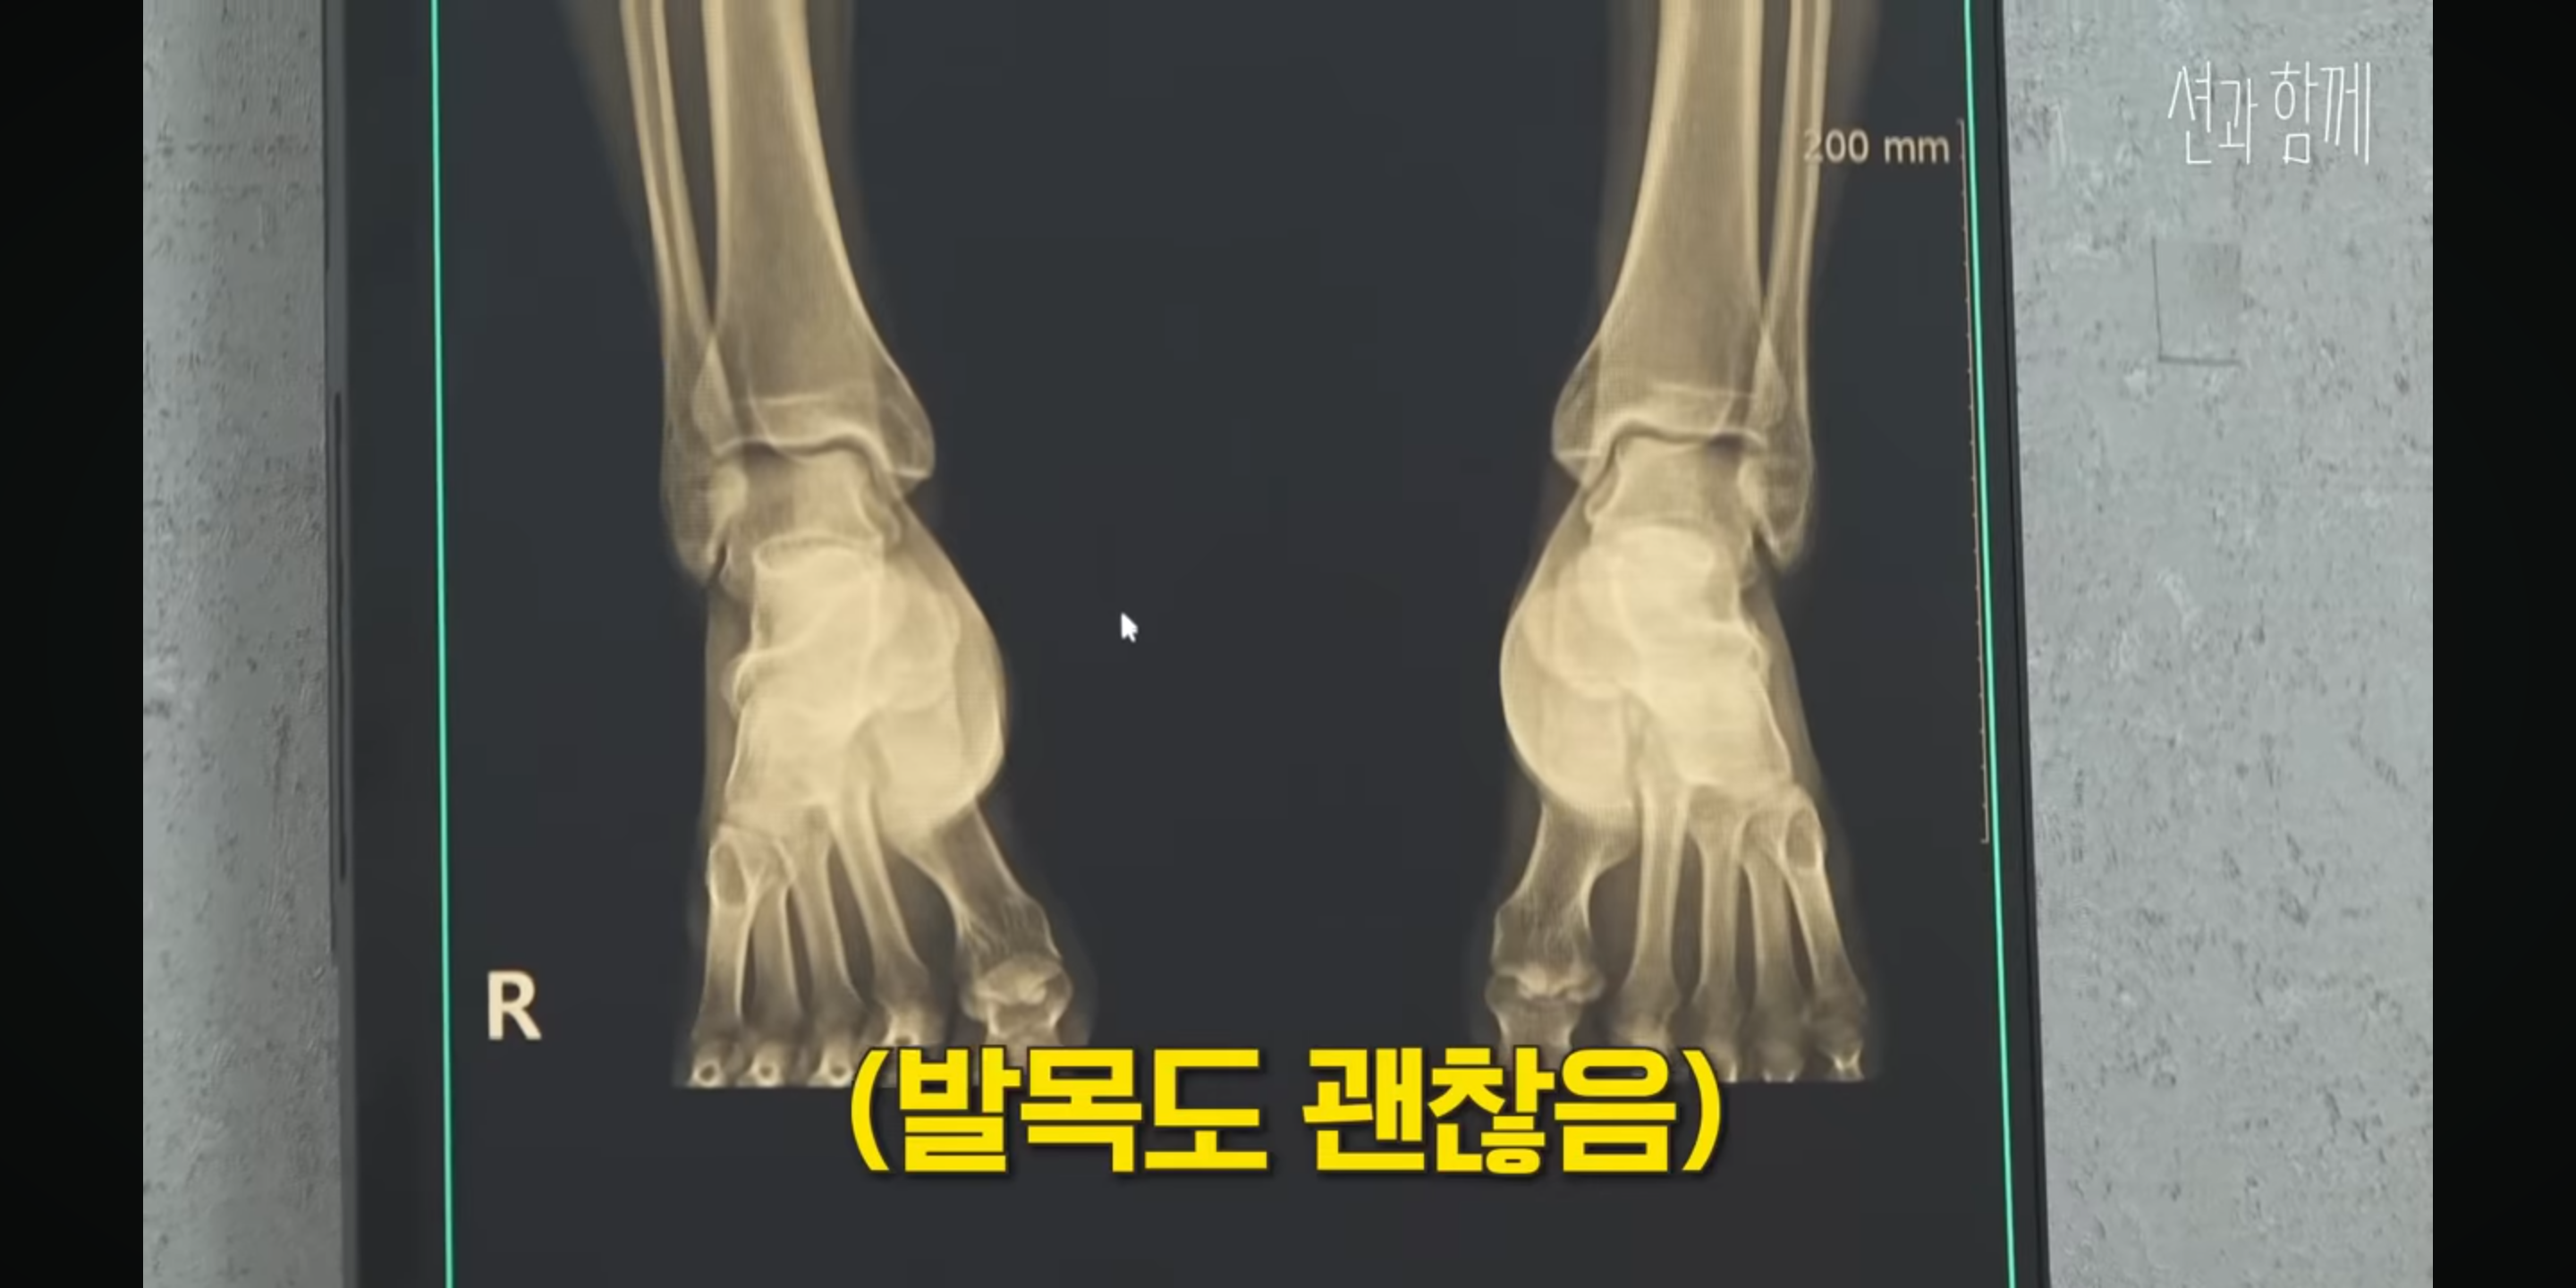

사람들이 하도 마라톤이랑 운동

너무 과하게 하니까 건강이랑

무릎 걱정된다고 해서

건강검진 받으러 감